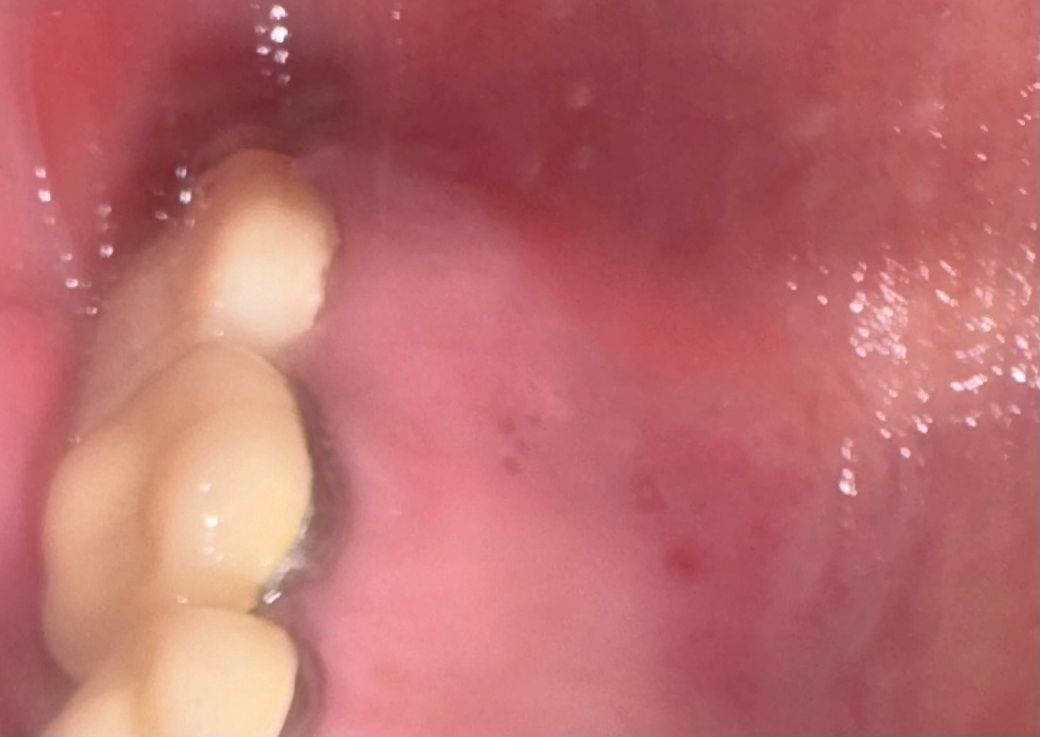

오른쪽 위 입 천장이 거슬려서 보니 이상한게 나있습니다

오른쪽 위 입 천장에 이상한게 나있습니다.

한 삼일정도 된 것 같은데 여전히 거슬려서 신경쓰이네요

항생제라도 챙겨먹어야 할까요 아니면 당장 병원 내원해야 할까요 통증은 전혀 없습니다

• 1번 째 사진

해당병변은 구내염일 가능성이 있어 보입니다 . 대개는 자연적으로 호전을 기대할수 있으나 증상이 지속되거나 다른 증상이 동반되기 시작한다면 구강내과나 이비인후과 진료를 받아보시기 바랍니다.